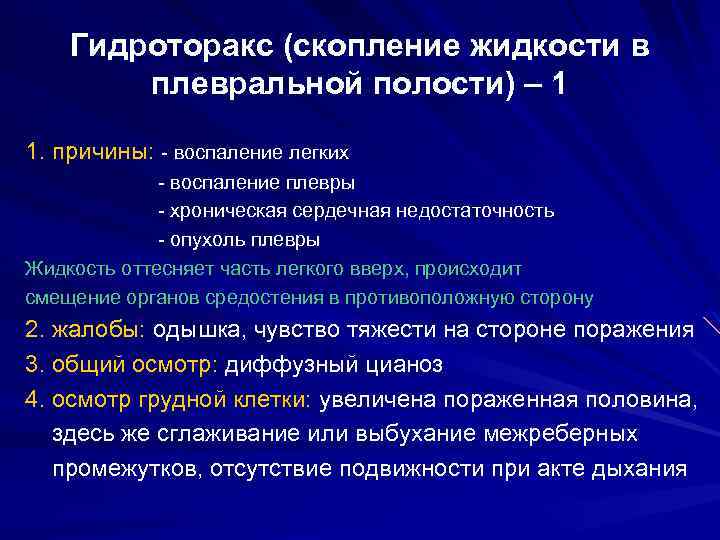

Дифференциальная диагностика заболеваний плевры